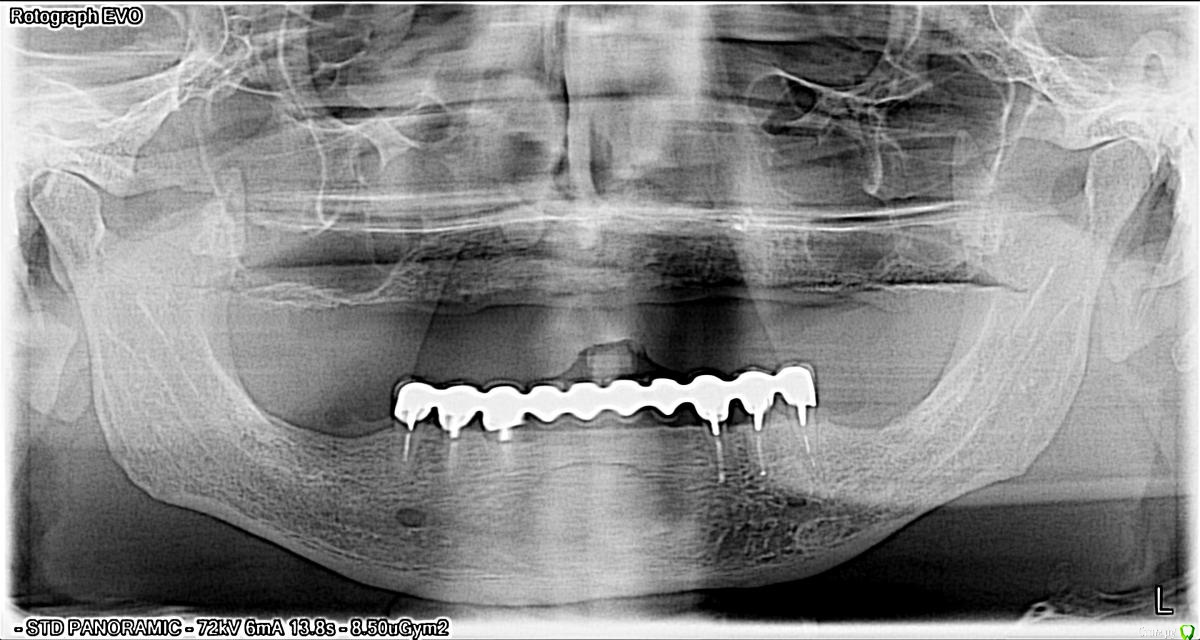

kemak Опубликовано 11 декабря, 2014 Поделиться Опубликовано 11 декабря, 2014 Добрый день коллеги, подскажите как вы считаете сколько и как в данном случае установить имплантатов? Ссылка на комментарий

kemak Опубликовано 11 декабря, 2014 Автор Поделиться Опубликовано 11 декабря, 2014 + 1, количество имплантов будет диктовать конструкция, имхо меньше 4 нет смыслая планирую 8 имплантатов, в области 15,14,12,11,21,22,24,25 и 16, 26- консоли. Ссылка на комментарий

max1183 Опубликовано 12 декабря, 2014 Поделиться Опубликовано 12 декабря, 2014 а зачем консоль если в зоне 6 есть место для импл я ставлю 1 3 4 5 6 или 7 Ссылка на комментарий

Чертков Александр Опубликовано 10 февраля, 2015 Поделиться Опубликовано 10 февраля, 2015 1,3,5 справа и слева. Более чем достаточно и "перегрузки" титаном не будет. Да, 6е консолями. А внизу какие планы? Ссылка на комментарий

Dr.Zoom Опубликовано 2 марта, 2015 Поделиться Опубликовано 2 марта, 2015 (изменено) 2,4,6 с обеих сторон и условно-съемный на фрезерованном каркасе и мультиках Изменено 2 марта, 2015 пользователем Dr.Zoom Ссылка на комментарий